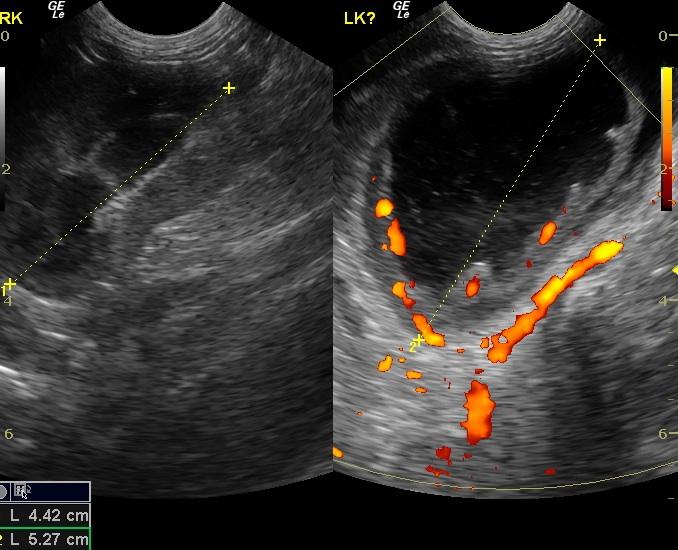

A 5-year-old FS DLH cat was presented for hiding at home and anorexia. Abnormalities on physical examination included a large urinary bladder and mild dehydration. Leukocytosis was present on CBC; blood chemistry was within normal limits. Survey abdominal radiographs showed left-sided renomegaly and a small right kidney.